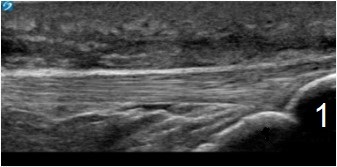

Knee Infrapatellar Tendon Image

Tibial Tuberosity